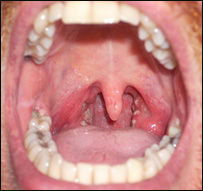

تانسلونه (هډي)، چې عام وګړي يې په ستوني کې اضافي غوښې بولي، په بدن کې دمکروب پروړاندې دفاعي دنده پرمخ بيايي، چې له دې امله ډېری وخت پخپله مکروبي کيږي. روغتيايي کارپوهان دتانسلونومکروبي کېدل نه يواځې ساري بلکې يوه ارثي ناروغي هم ګڼي. دستوني، غوږ او پزي متخصص ډاکتر صديق الله رښتين دنورو ترڅنګ د خولې او غاښونو پاکوالي ته نه پاملرنه هم ددې ناروغۍ لامل وګاڼه. هغه کسان، چې تانسلونه يې مکروبي شوي وي، دسختې تبې او ځان دردۍ ترڅنګ يې د ستوني لاندنۍ برخه کې پړسوب هم ليدل کيږي.  | | | دتانسلونومکروبي کېدل نه يواځې ساري بلکې يوه ارثي ناروغي هم ګڼي. |

که ددې ناروغۍ په درملنه کې بې پروايي وشي،مکروب يې په وينه کې ګډ او دروماتيزم او نورو ناروغيو دپيداکېدولامل هم کيږي. ددې ناروغۍ څخه دمخنيوي په موخه روغتيايي کارپوهان دخولې دپاک ساتلوترڅنګ له ډېروغوړو، خوږواو مرچوخوړلوډډه کول ګټوربولي. |